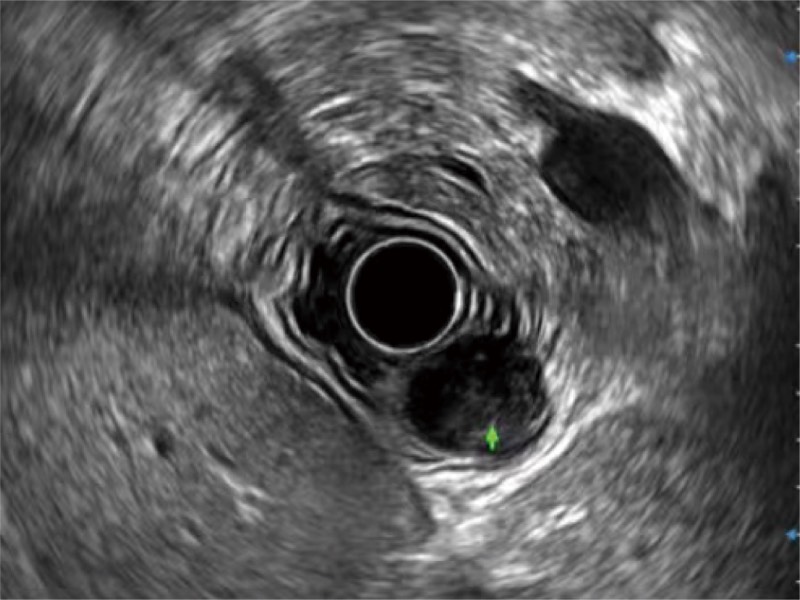

食管內(nèi)間質(zhì)瘤清晰顯像

清晰顯示膽總管及周?chē)芊植?/p>

肝左葉和肝靜脈的橫截面